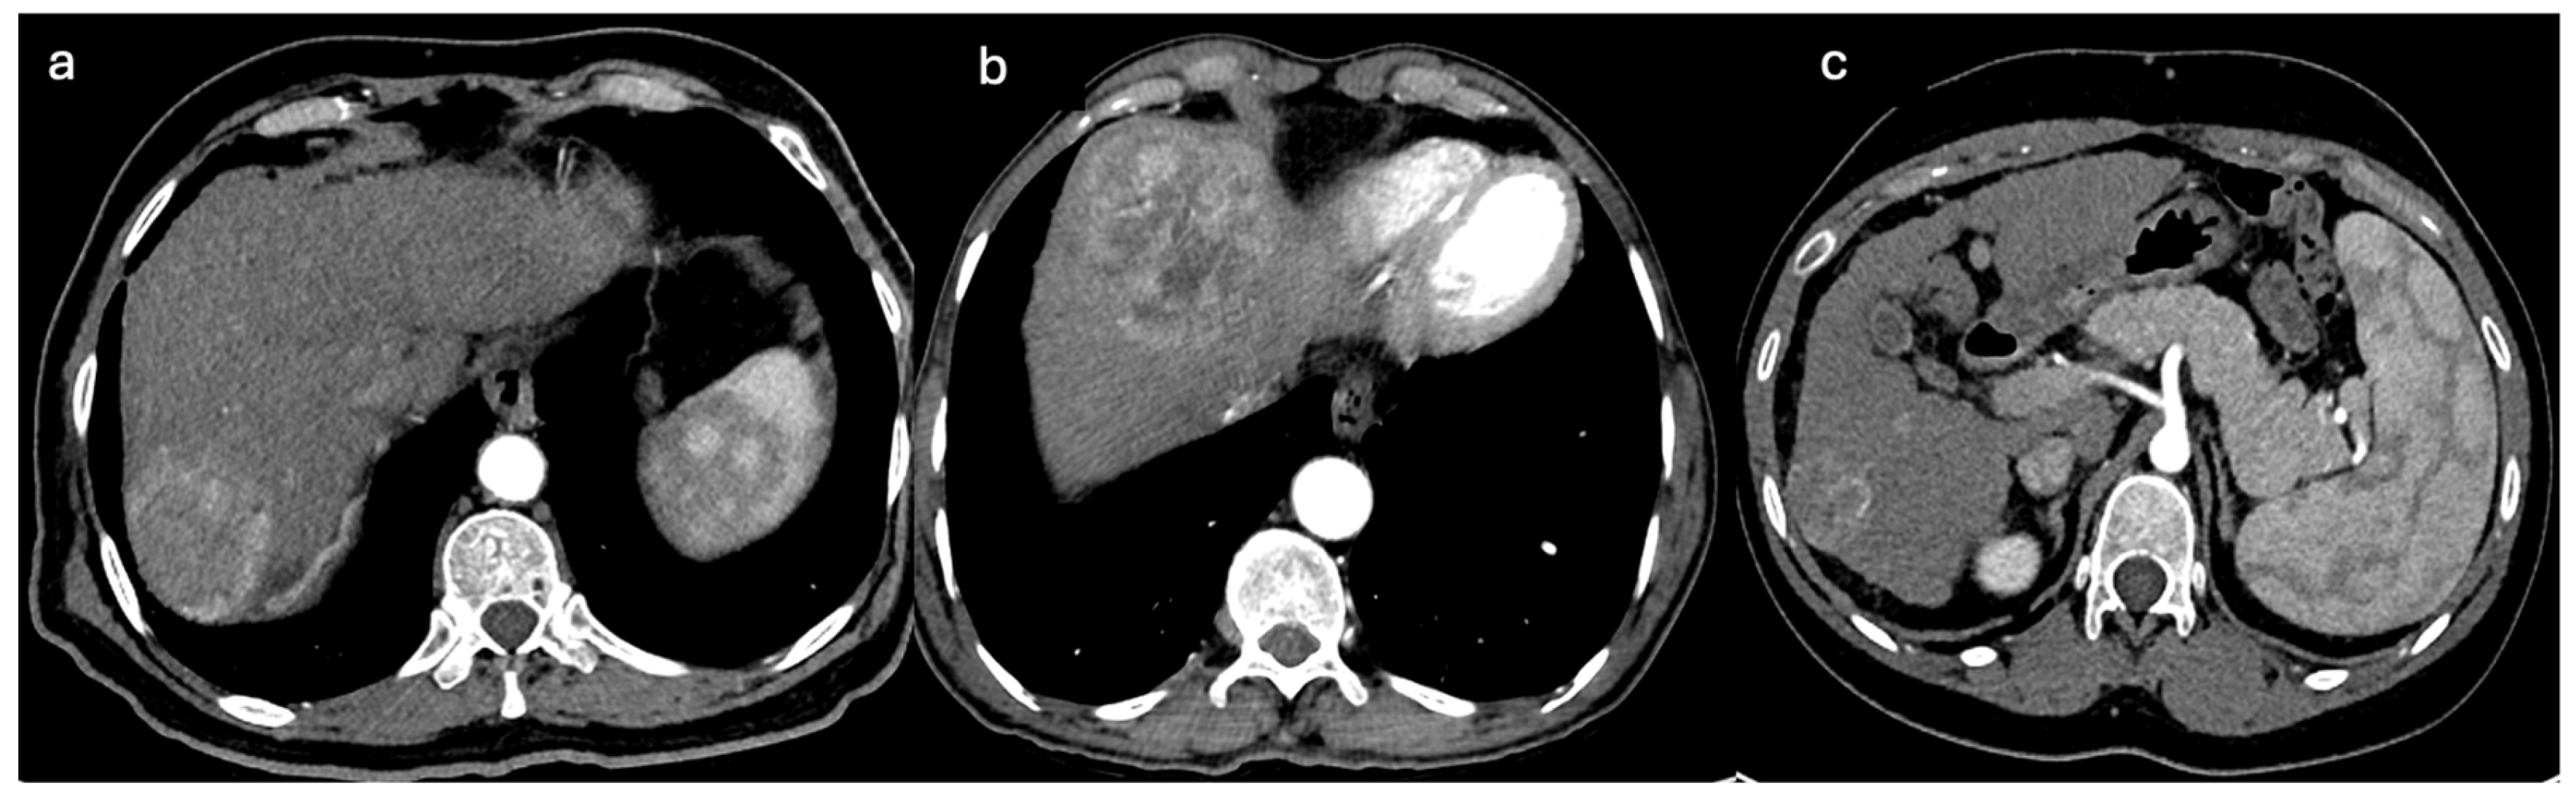

- Accessory extra-mesenteric arteries: Tumors that are located anteriorly at liver dome segments 2, 4A, and 8 may receive accessory supply from the internal mammary artery, a branch of the right subclavian artery. However, HCC located posteriorly at liver dome segments 8, 7, and 2 and the caudate may receive accessory supply from the inferior phrenic artery, a branch of the celiac trunk or directly originating from the abdominal aorta [64]. A subcapsular tumor near the ribs may receive accessory supply from intercostal arteries, as shown in Figure 5 [65].